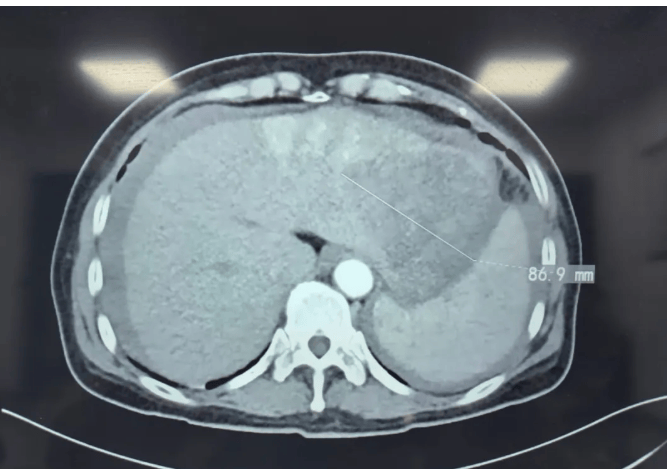

术前影像图

这个患者可能是肝癌,且可能是肝癌破裂出血。这可是个急症,他随时可能出现致命性大出血。我拿起他在当地医院做的平扫CT,发现肝左叶可见低密度影。如果任由他继续去郑州,随时会因大出血而危及生命。

和患者家属充分沟通后,立即办理住院手续,急诊行增强CT和血液检查。增强CT和血液检查显示肝癌破裂出血。这证实了我的判断。